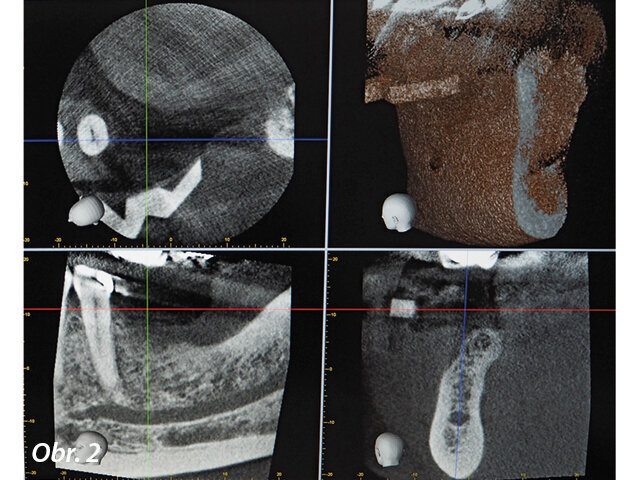

V našem případě byla tedy vytvořena šablona NaviStent s umístěním výchozího bodu a dva týdny před chirurgickým zákrokem byl pořízen CBCT sken (obr. 2). Plán ošetření byl vytvořen ihned po skenování (obr. 3) za přítomnosti pacienta. Mohl tak vidět navrhované ošetření zobrazené softwarem Navident a ocenit velkou péči věnovanou dosažení optimálního umístění implantátu s minimálním rizikem potenciálních komplikací (obr. 4). Pacient byl ohromen a uklidněn díky nejmodernější technologii.

Dynamická navigace Navident přesně vede chirurga při preparaci a umístění implantátu do předem určené pozice (obr. 1). To mu umožňuje dosáhnout větší přesnosti a jistoty než dříve při použití konvenčních protokolů. Používá se zde jednoduchá virtuální šablona (NaviStent), která drží výchozí bod při pořizování CT skenu a zajišťuje referenci na čelisti (JawTag) pro navigovanou osteotomii.

CBCT sken byl pořízen dva týdny před chirurgickým zákrokem